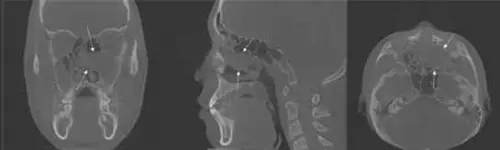

「사례1」14세 남아의 왼쪽 상악동에 생긴 점액낭종 (Mucocele)

「사례2」6세 남아의 오른쪽 접형동에 생긴 섬유형성이상